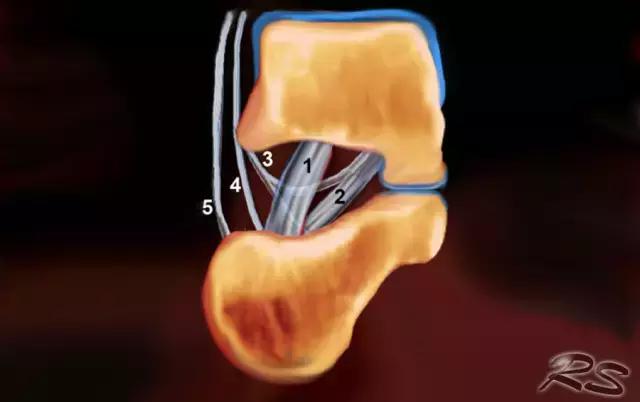

跗骨窦是锥形空腔,在后内侧到前外侧方向上延伸。它位于距骨的颈部和跟骨的前上表面之间的脚的外侧面。跗骨窦内侧继续作为跗管,这是距骨与跟骨间一个漏斗形的空间。它包含脂肪,动脉吻合,关节囊,神经末梢和五个韧带结构 - 下伸肌视网膜的内侧,中间和侧根; 颈韧带; 和骨间骨骨膜韧带(图)。

这个空间可以是脚部疼痛在跗骨窦综合征的原因。治疗的第一步是用epomedrol和局部麻醉剂(利多卡因)的混合物封闭治疗。这对于外科医生在非引导方法中可能是挑战性的,但是用超声引导相当容易和准确地实现。

超声引导的跗骨窦的注射在右手侧与外侧入路。探头保持在冠状倾斜平面中。针沿着探头的长轴引入。

使用超声波可以容易地观察窦性骨壁。患者转向对侧,将待治疗的足以其内侧表面靠在桌面上,脚的外侧位于最上面。探头保持在关于脚的冠状平面中。